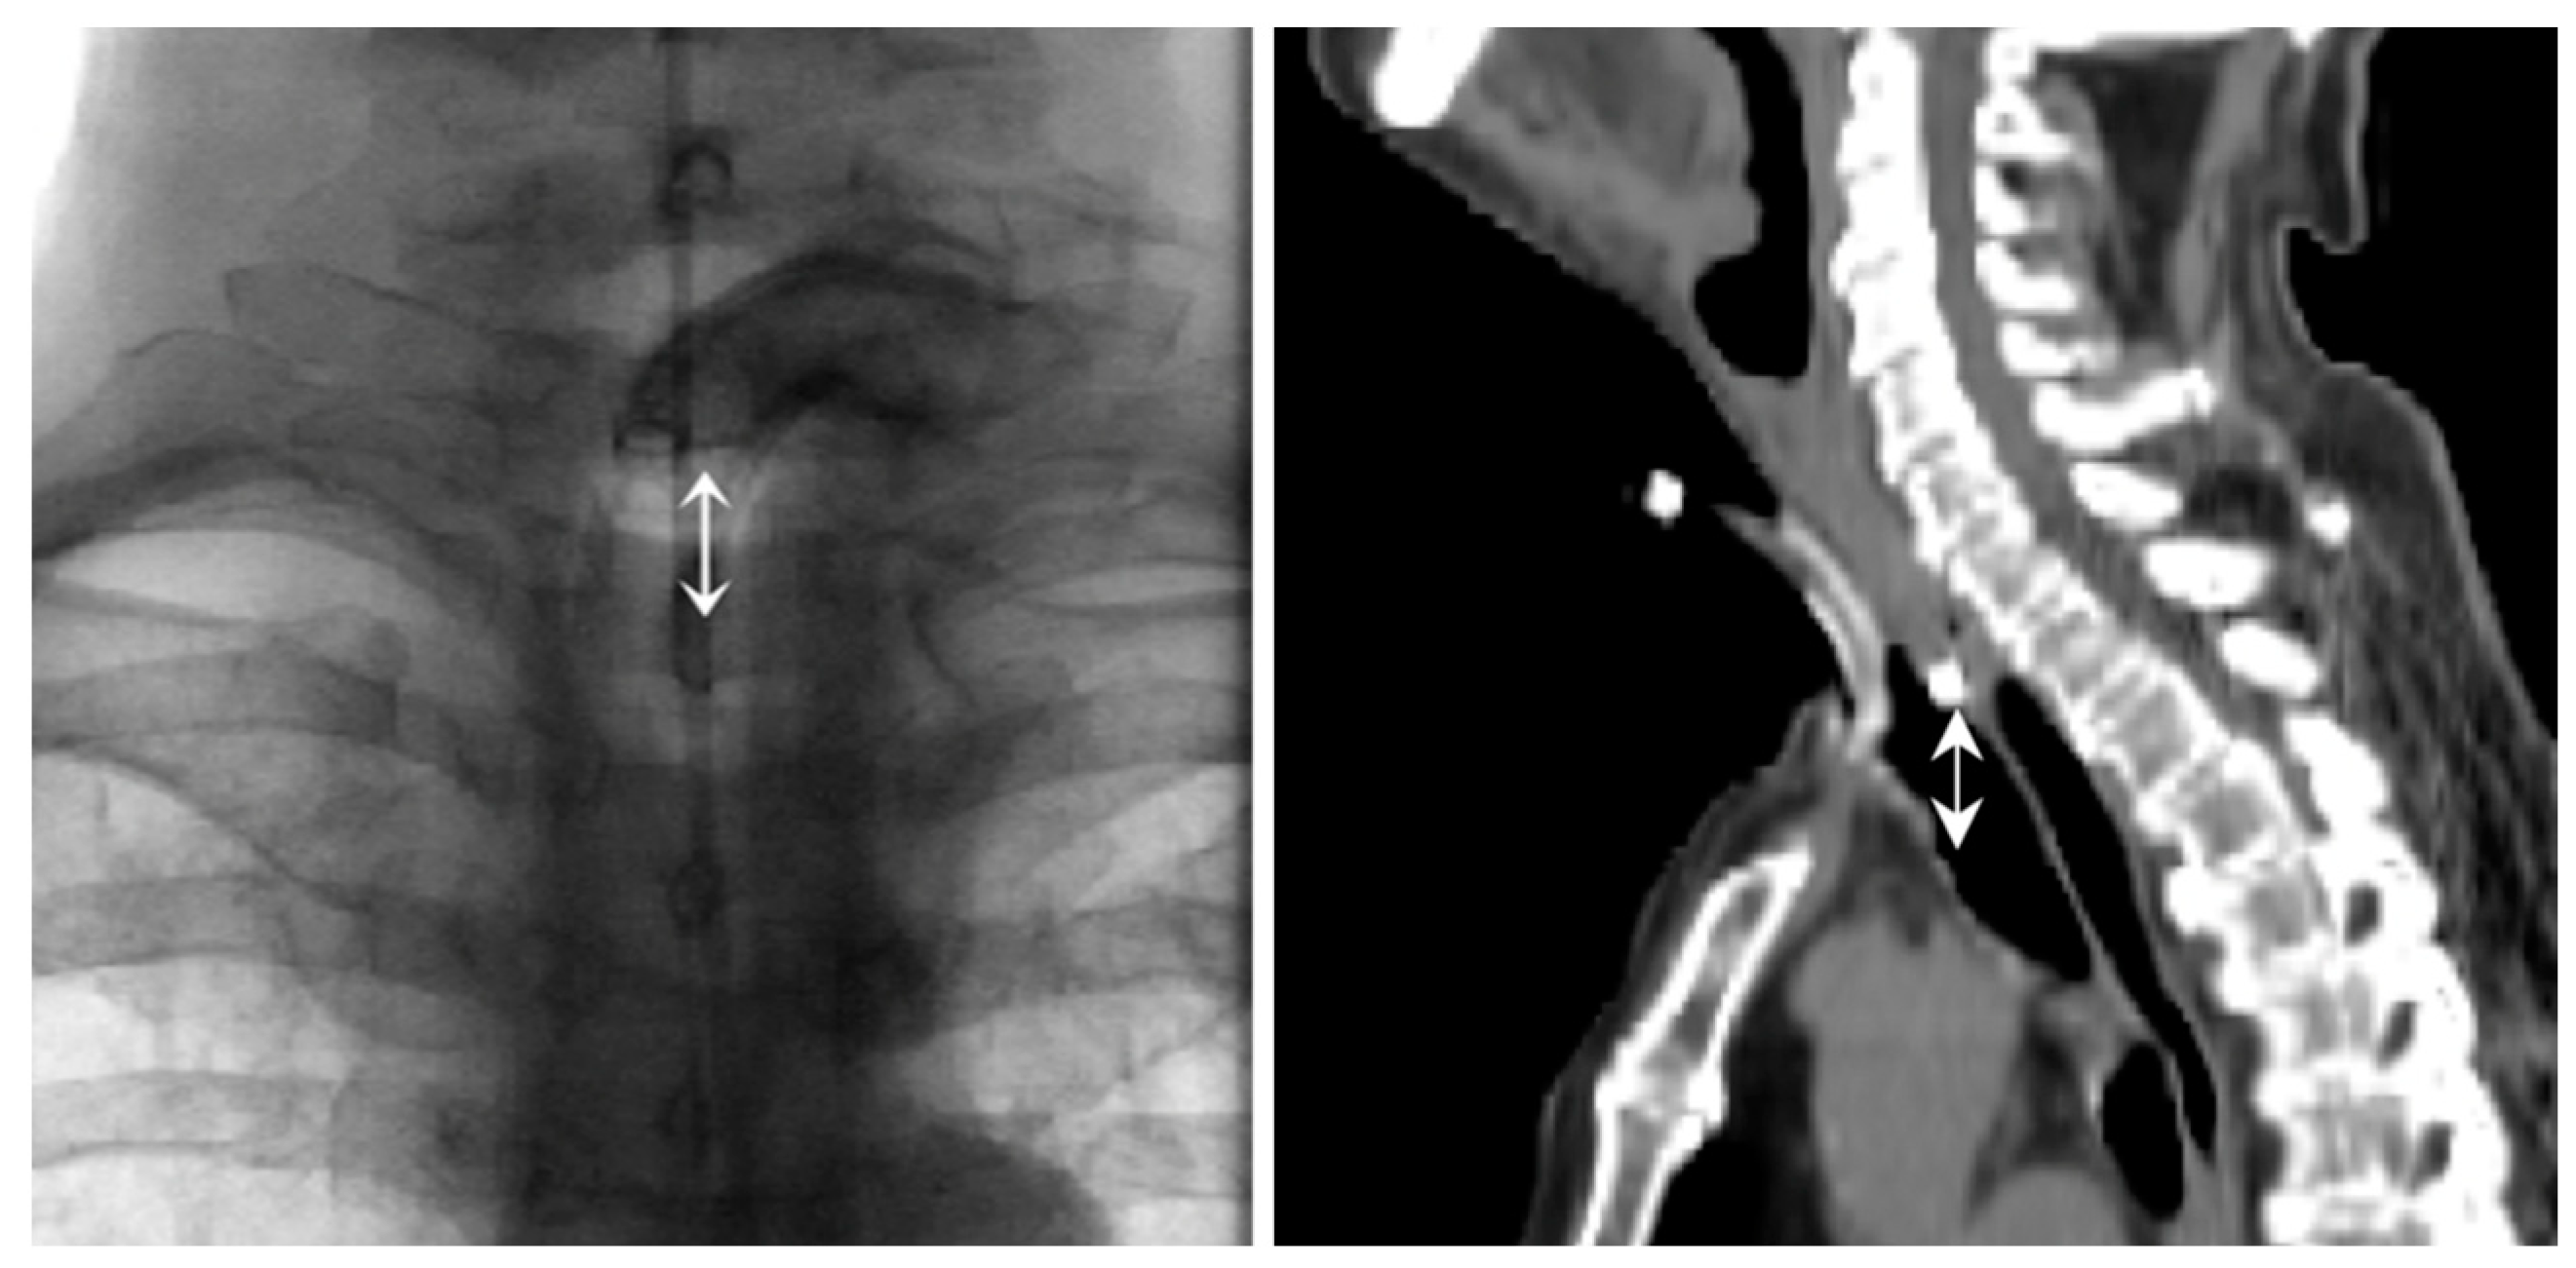

| Distance Voice prothesis—manubrium (cm) | |||

| >1.5 cm, n (%) | 23 (37) | 69 (63) | <0.001 |

| Median | 1.21 | 1.90 | |

| Mean ± SD | 1.66 ± 1.14 | 1.83 ± 1.36 |